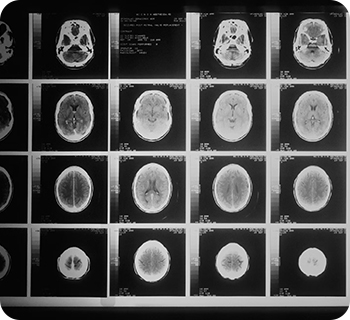

MRI, CT, 등 최신 진단 장비를 통해 정밀한 검사와 진단을 제공합니다.